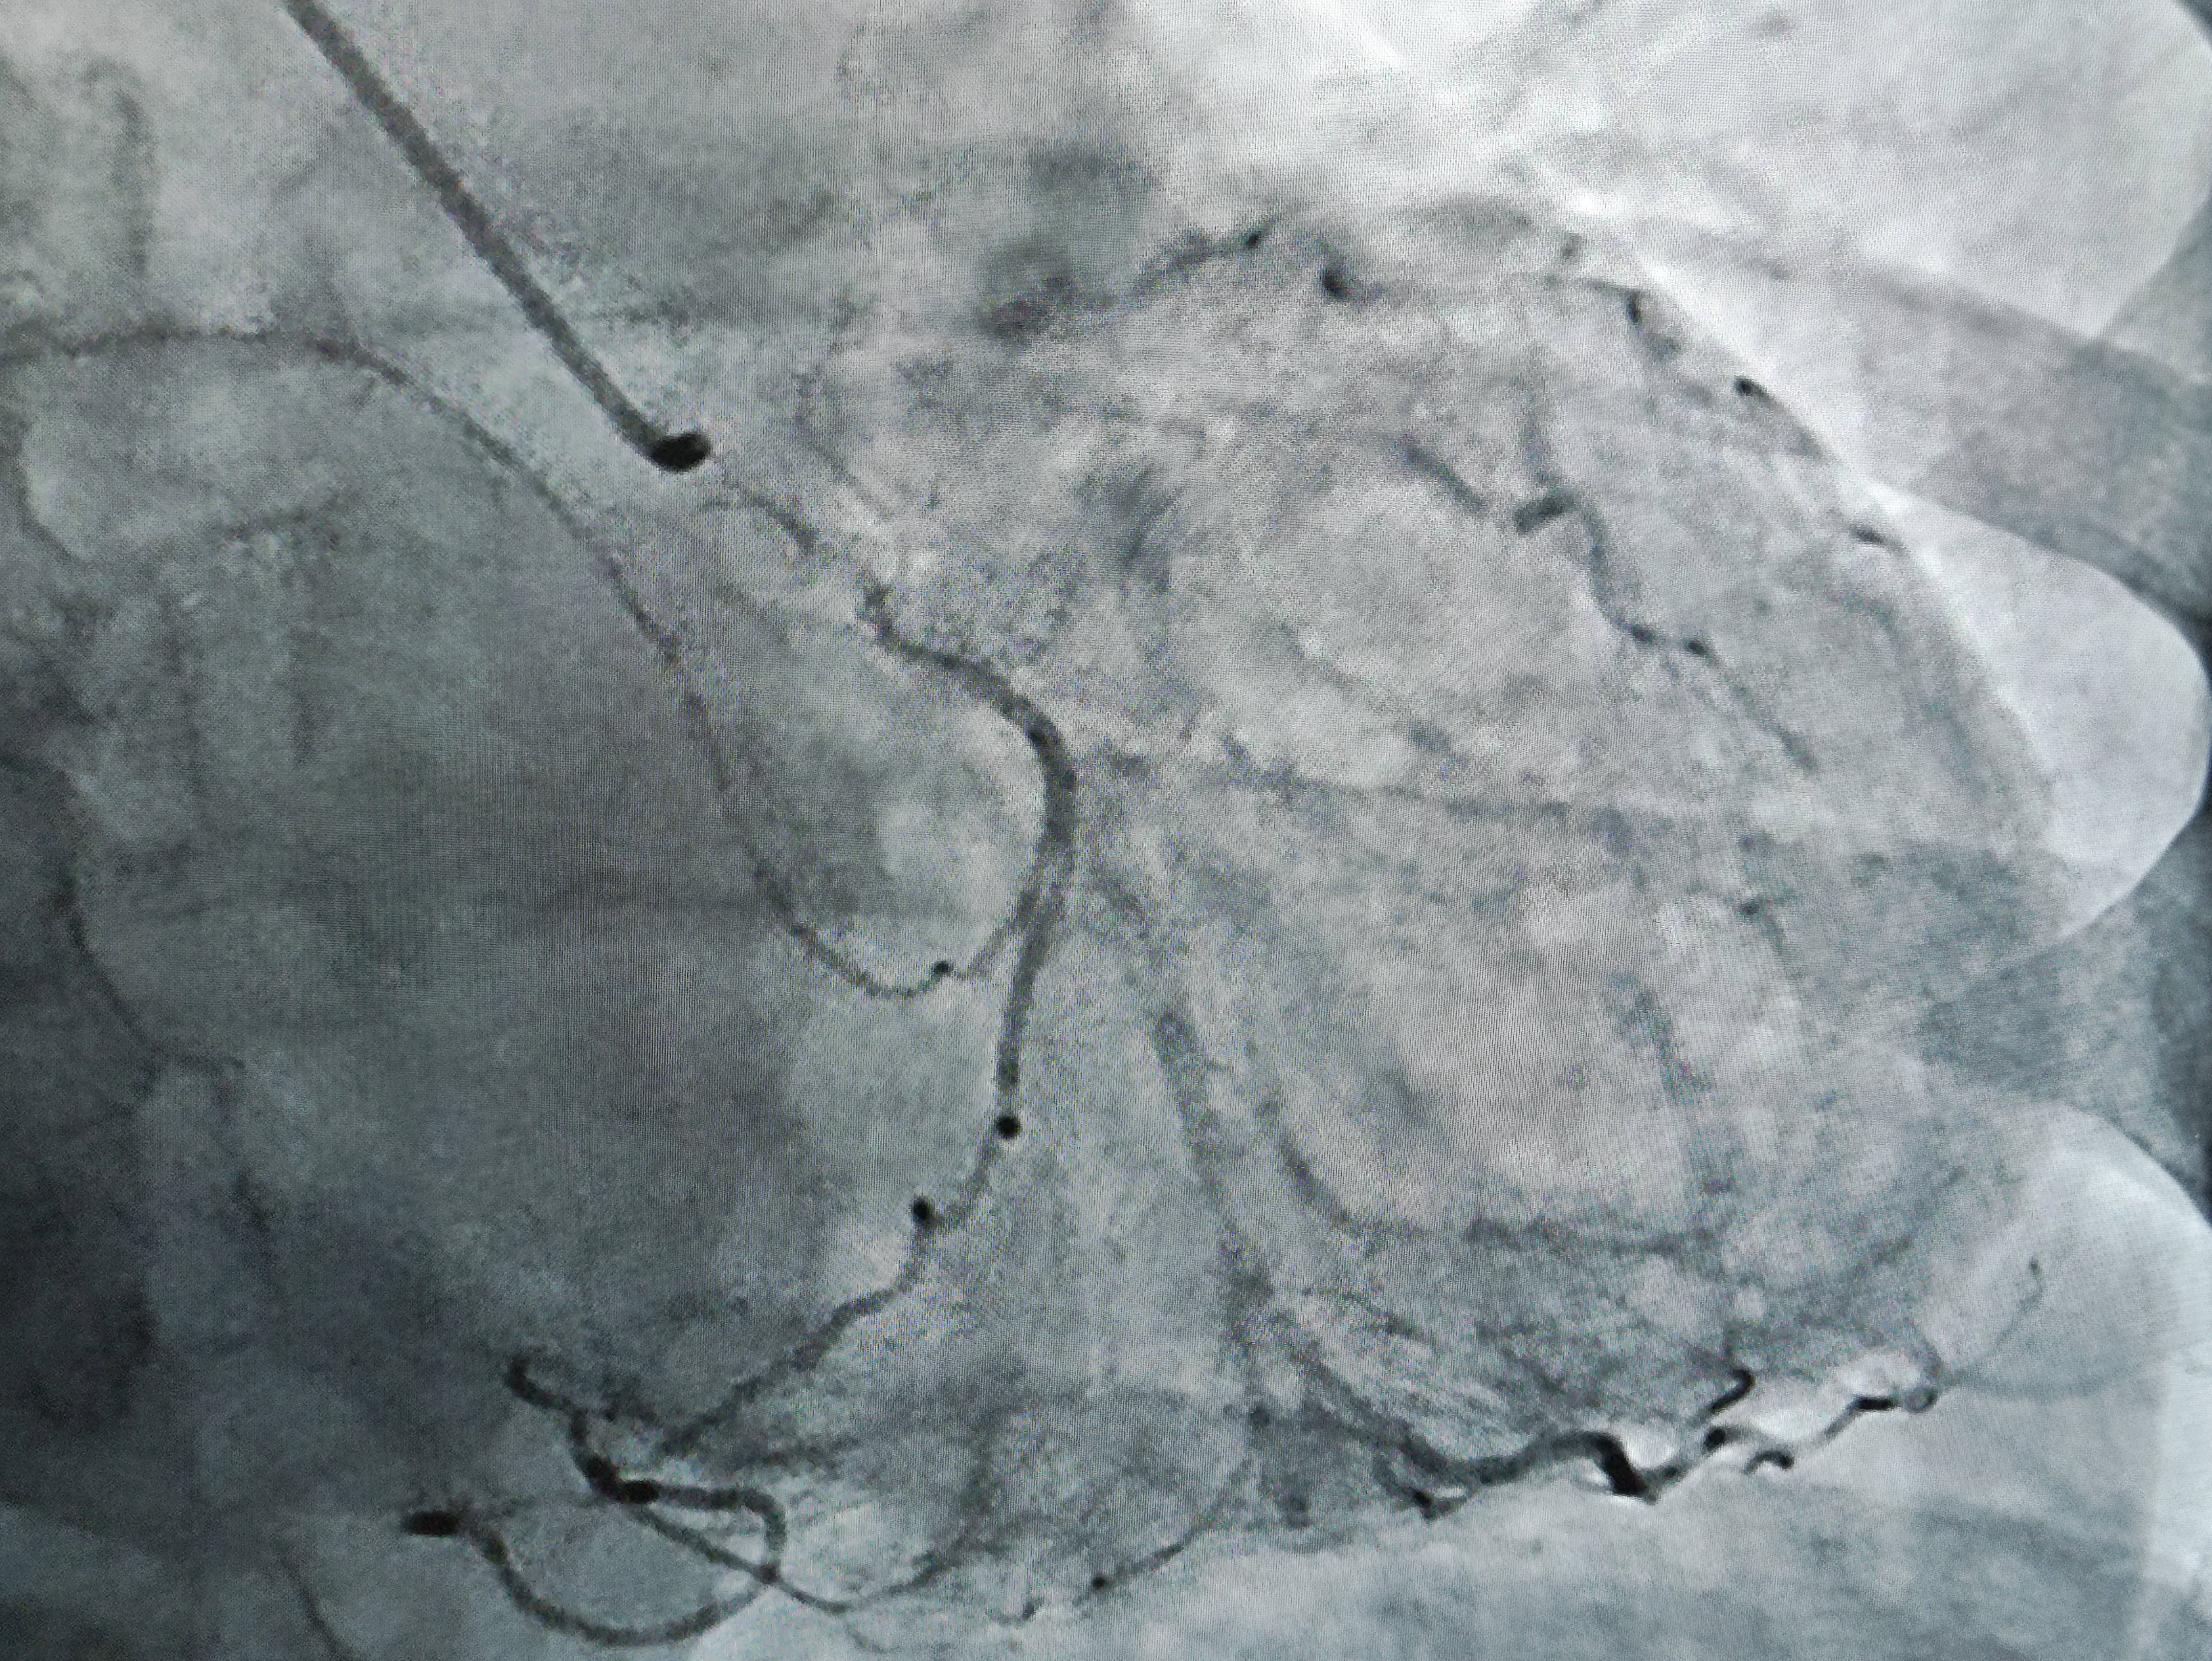

Первую коронарографию пациентке с ишемической болезнью сердца 4 сентября выполнил врач по рентгенэндоваскулярным диагностике и лечению отделения РХМДЛ, к.м.н. Евгений Андреевич Глухов.

«В ходе ангиографического исследования с помощью катетера в сосуд вводят йодосодержащее рентгеноконтрастное вещество, которое не пропускает рентгеновские лучи и, смешиваясь с кровью, делает просвет сосуда видимым под рентгеном, - рассказал Евгений Андреевич. - Например, при ишемической болезни сердца исследованию подвергаются коронарные сосуды, поэтому данную разновидность исследования называют коронарографией. При необходимости ее сочетают с эндоваскулярными или внутрисосудистыми видами хирургических вмешательств – стентированием, ангиопластикой».